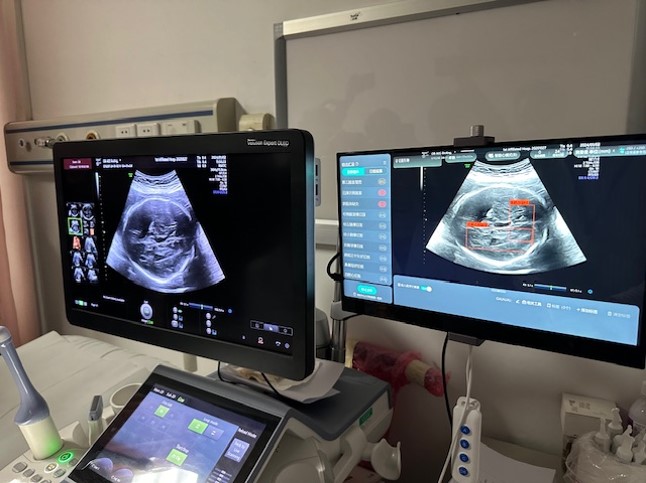

“大湾区医疗人才交流计划”首次实现双向交流。医管局透露,自前年9月推出计划后,今年1月首次派出香港放射师、物理学家及护理服务团队,赴大湾区多间三甲医院进行为期3至12日的交流活动。当中3名参与交流的医疗人员向星岛环球网指,对内地医院应用人工智能方面印象深刻,冀日后有更多机会进行双向交流。基督教联合医院高级物理学家陈小强指,若以人手勾划肿瘤轮廓,往往要花费2至3小时,但内地医院利用自主研发的人工智能软件处理相关图像只需2至3分钟,能有效提升工作效率。

▲香港医疗人员到内地交流,了解当地先进治疗仪器及技术。 医管局提供

▲香港医疗人员到内地交流,了解当地先进治疗仪器及技术。 医管局提供

陈小强指,不少治疗程序都需要用上物理学家专长,如用作治疗和诊断的辐射、治疗癌症的电疗等。以肿瘤科为例,病人完成电脑扫描后,需要再勾划出肿瘤及正常细胞的分别,而内地的人工智能平均只需2、3分钟已可完成勾划,医生只需负责最后的检验和修改程序。他坦言,香港虽然也有采用人工智能技术,但多数以外国购入的软件进行,“而海外的软件多参照外国人的病例研发,而国内研发软件则以华人病例为本,模型准绳度可能较高。”他亦赞今次交流令两地医疗人员,能分享彼此技术的优劣之处,可望互补长短。

▲香港医疗人员到内地交流,了解当地先进治疗仪器及技术。 医管局提供